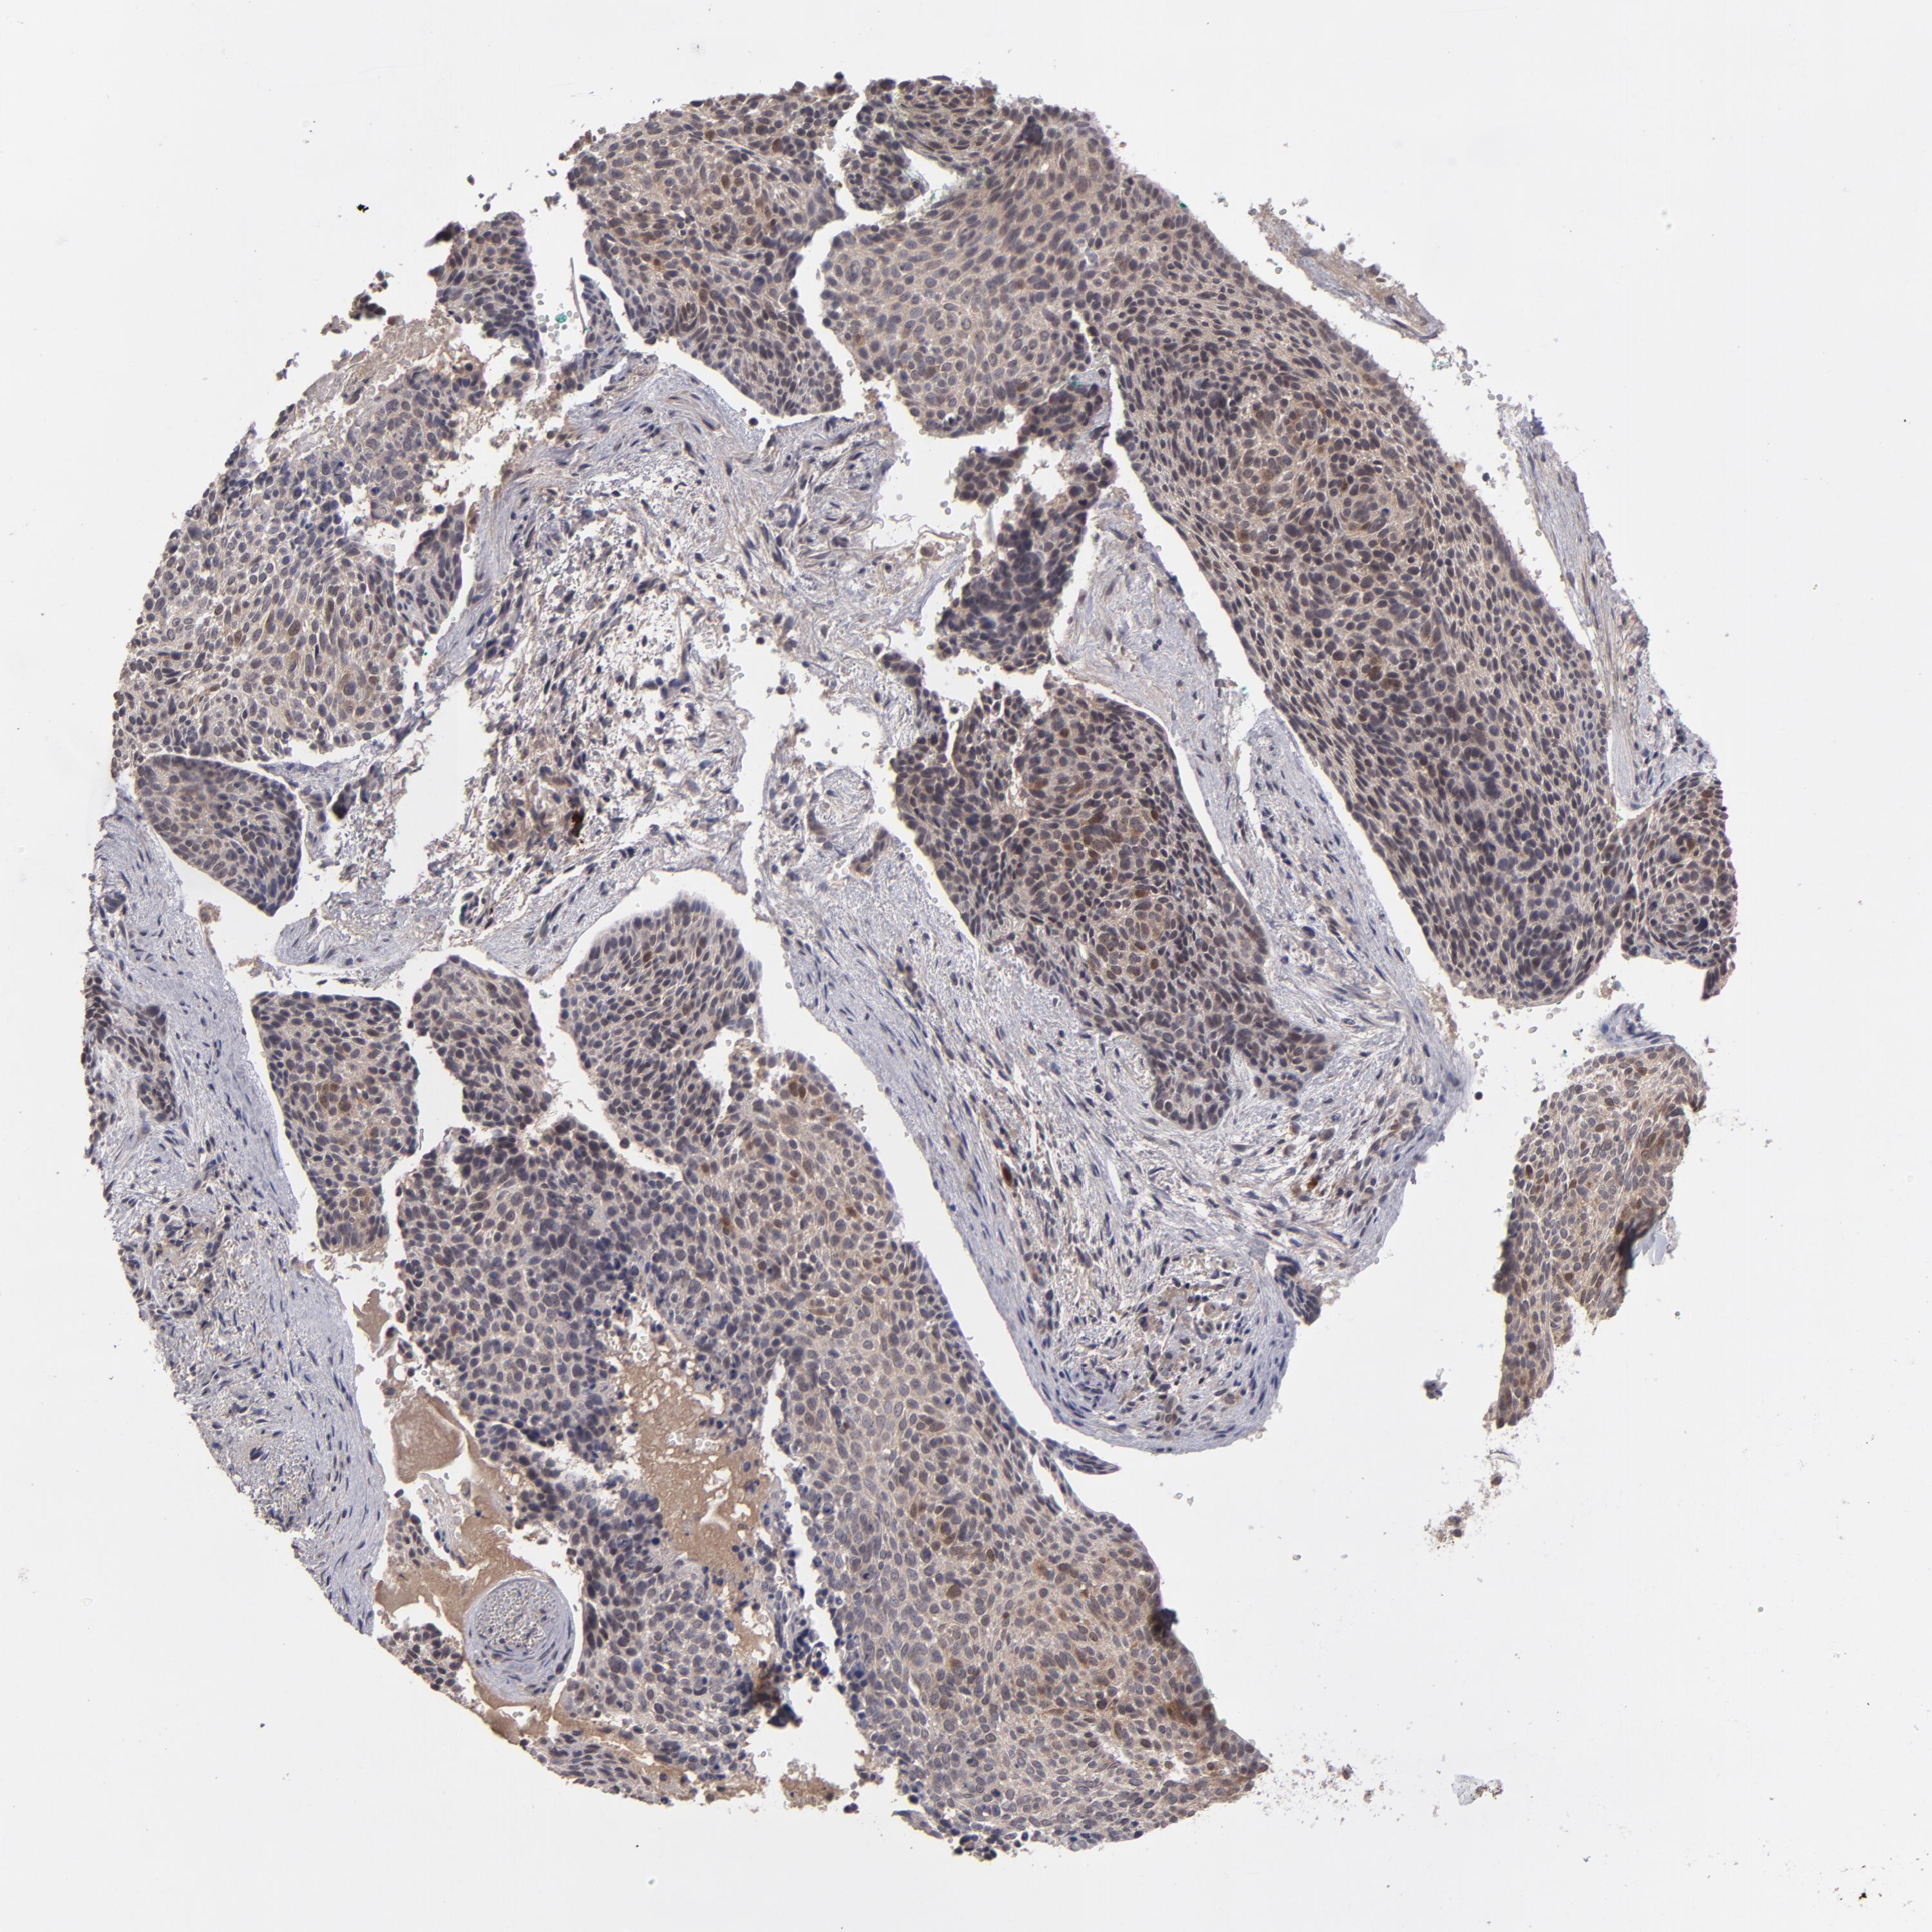

SKIN CANCER - Protein expressioni

A mouse-over function shows sample information and annotation data. Click on an image to view it in a full screen mode. Samples can be filtered based on level of antibody staining by selecting one or several of the following categories: high, medium, low and not detected. The assay and annotation is described here.

Antibody stainingi

Antibody staining in the annotated cell types in the current human tissue is reported as not detected, low, medium, or high, based on conventional immunohistochemistry profiling in selected tissues. This score is based on the combination of the staining intensity and fraction of stained cells.

Each image is clickable and will lead to virtual microscopy that enables deeper exploration of all samples and also displays staining intensity scores, fraction scores and subcellular localization as well as patient and tissue information for each sample.

Antibody HPA074922

Antibody CAB002784

Basal cell carcinoma

Squamous cell carcinoma, NOS